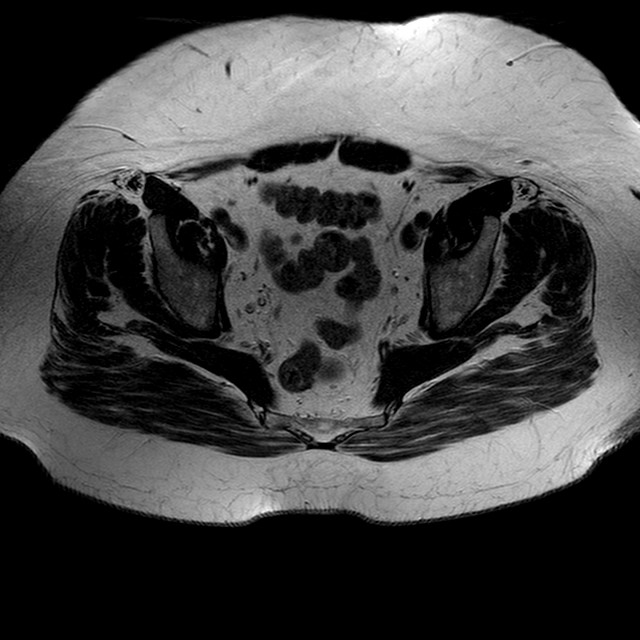

Esami: RMN BACINO

T2w TSE

Evidenti e simmetriche alterazioni osteofitosiche in regione coxo femorale con riduzione delle rime articolari. Degenerazione completa del cercine glenoideo. Non attuali segni di versamento articolare. Non segni di edema osseo che escludono attuale algodistrofia od osteonecrosi. Lieve e simmetrica riduzione del trofismo della muscolatura glutea.